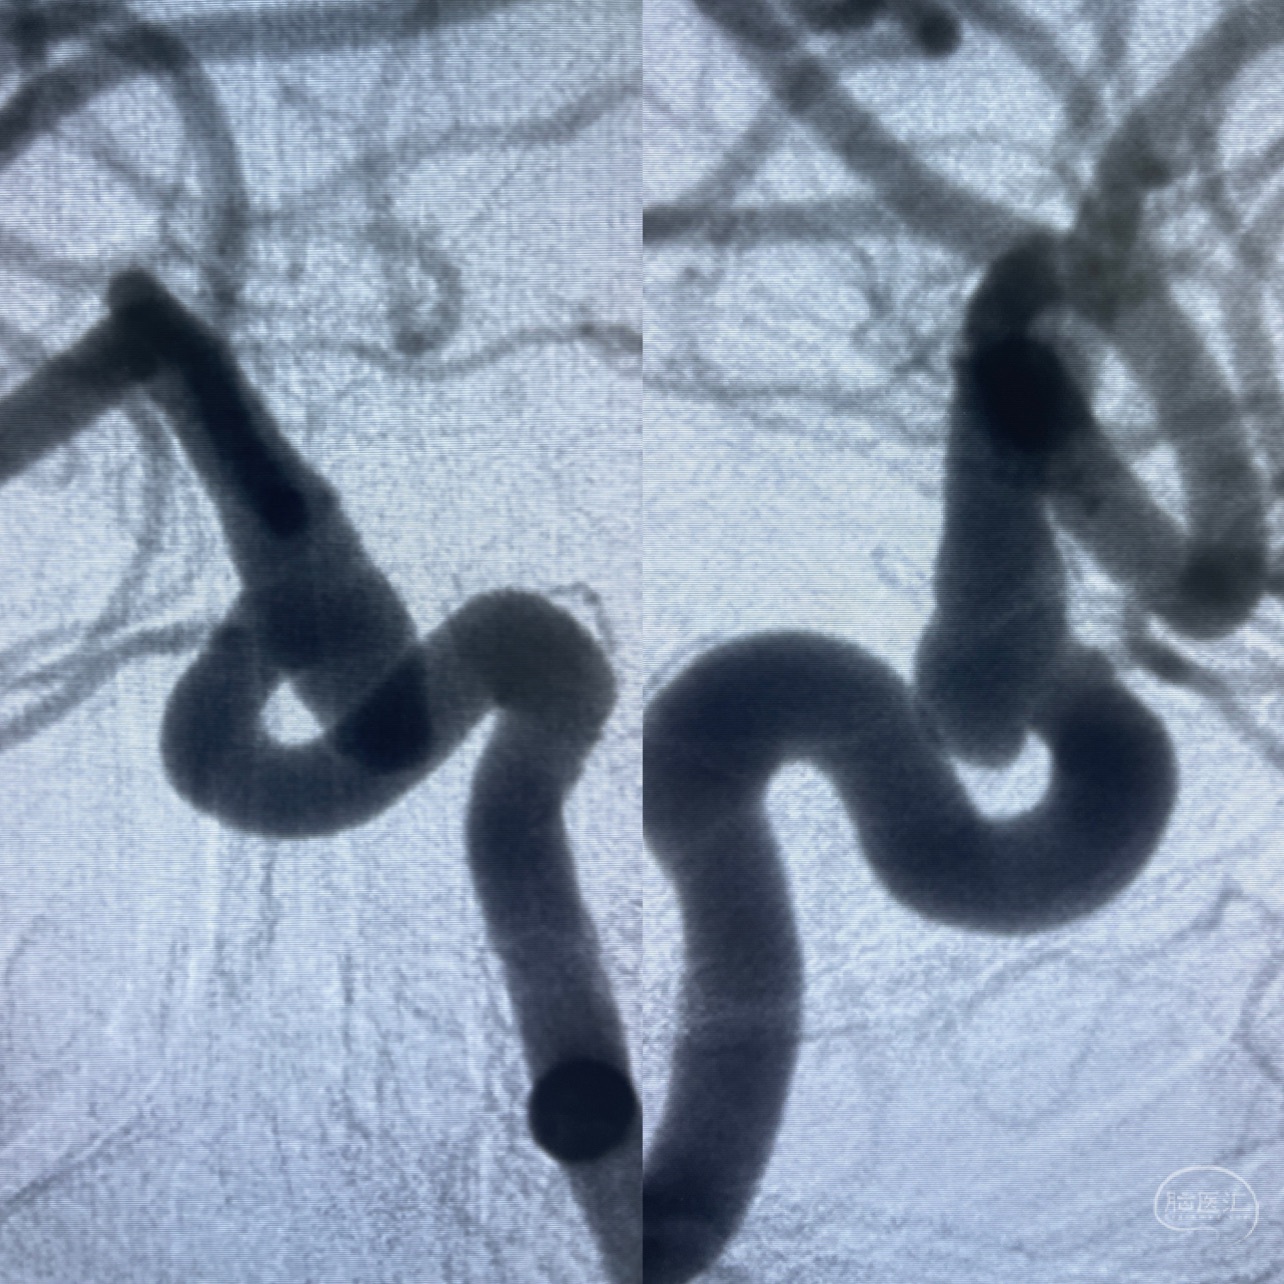

CTA示:右侧颈内动脉C6段见指向下方的突起,余左侧颈内动脉、双侧椎动脉、大脑前动脉、大脑中动脉、大脑后动脉及基底动脉走形正常,未见明显扩张及狭窄,局部未见明显瘤样扩张。

看原图,应该有两侧动脉瘤😅

2023-07-27全脑血管造影:双侧颈内动脉眼动脉段动脉瘤,右侧较大

2023-08-01全麻下行双侧颈眼动脉瘤支架辅助栓塞

- pipeling4.5-20mm

- pipeline 4.0-20mm